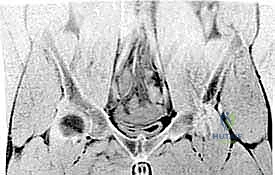

- التصوير بالرنين المغناطيسي (MRI): هو المعيار الذهبي (Gold Standard) في تشخيص آلام الأربية المعقدة. يطلب الدكتور هطيف صور رنين مغناطيسي عالية الدقة (High-resolution MRI) لتقييم مدى تضرر وتر المقربة الطويلة، واستبعاد التهاب العظم العاني (Osteitis Pubis)، والتأكد من سلامة مفصل الورك والأنسجة الرخوة المحيطة.